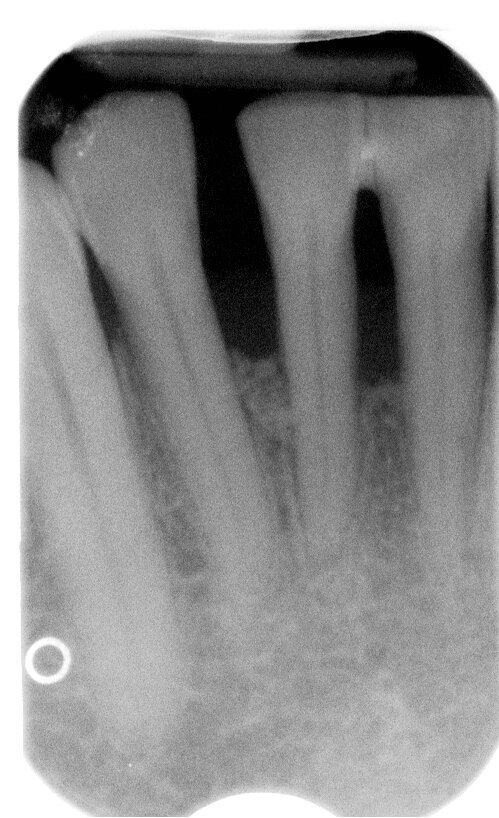

Il Paziente è stato intercettato in visita con diagnosi di parodontite cronica generalizzata da moderata a severa a seconda dei siti. È stata eseguita la terapia non chirurgica in regime di Full mouth disinfection in unica seduta seguita da controlli settimanali fino al raggiungimento della guarigione a 2 mesi dalla strumentazione. In tale fase sulla base della valutazione dei siti con PD>5 mm e dell’anatomia dei difetti infra-ossei o sovra ossei presenti viene normalmente discussa con il paziente la fase di chirurgia correttiva, se necessaria. Nel Paziente in questo caso residuava a livello di 41 un difetto infra-osseo (Figg. 6a-6c).

Fig. 6c - Radiografia iniziale.